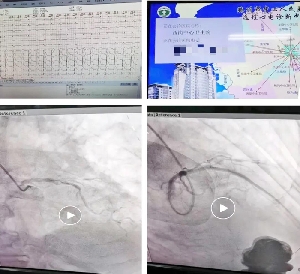

完美配合 只為初“心”——我院胸痛中心成功救治1例急性心肌梗死···

9月23日9:30分,西崗中心衛(wèi)生院通過遠程心電網(wǎng)絡(luò)發(fā)現(xiàn)一例急性緊急梗死患者,胸痛中心聽班電話聯(lián)系網(wǎng)絡(luò)醫(yī)院醫(yī)生及患者家屬,并與患者家屬溝通后,啟動胸痛中心綠色通道,120救護車“雙繞”導(dǎo)管室,10:40分于前降支成功植入支架1枚,門球時間30分鐘,患者安返監(jiān)護病房進一步救治。自我院創(chuàng)建胸痛中心以來,對胸痛患者的識別